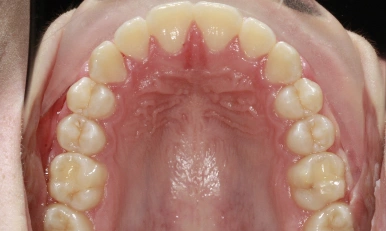

Patient Results